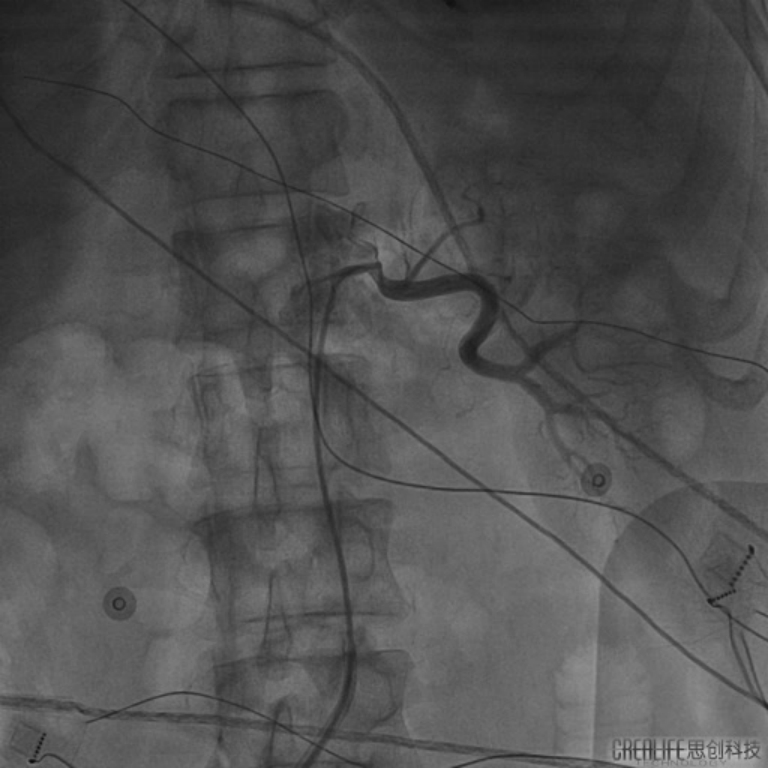

在充分考虑患者及其家属意愿后,汤宝鹏教授及李耀东教授经过术前讨论为患者量身定制了缜密的手术方案。手术由李耀东教授主刀采用导管微创介入手术,通过在X线下对左右肾动脉血管进行造影定位,同时在三维可视系统的指导下对肾动脉进行三维重建并进行射频消融。消融治疗通过在患者右腿植入一根直径大约2.5mm的管路进行,每次消融仅需30秒,18次治疗的手术过程约一个小时,且患者全程保持清醒,显著提升了患者的治疗体验。

(图为在三维可视系统下对肾动脉进行重建及消融治疗)